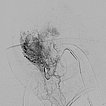

In the transarterial control angiography via the 4F diagnostic catheter, the infantile hemangioma is not perfused anymore. The typical DSA image of a “defoliated tree” is now shown.

Overview angiography via the common carotid artery after removal of the venous blocking balloon displays a virtually completely devascularized infantile hemangioma. The intracerebral circulation is normal.